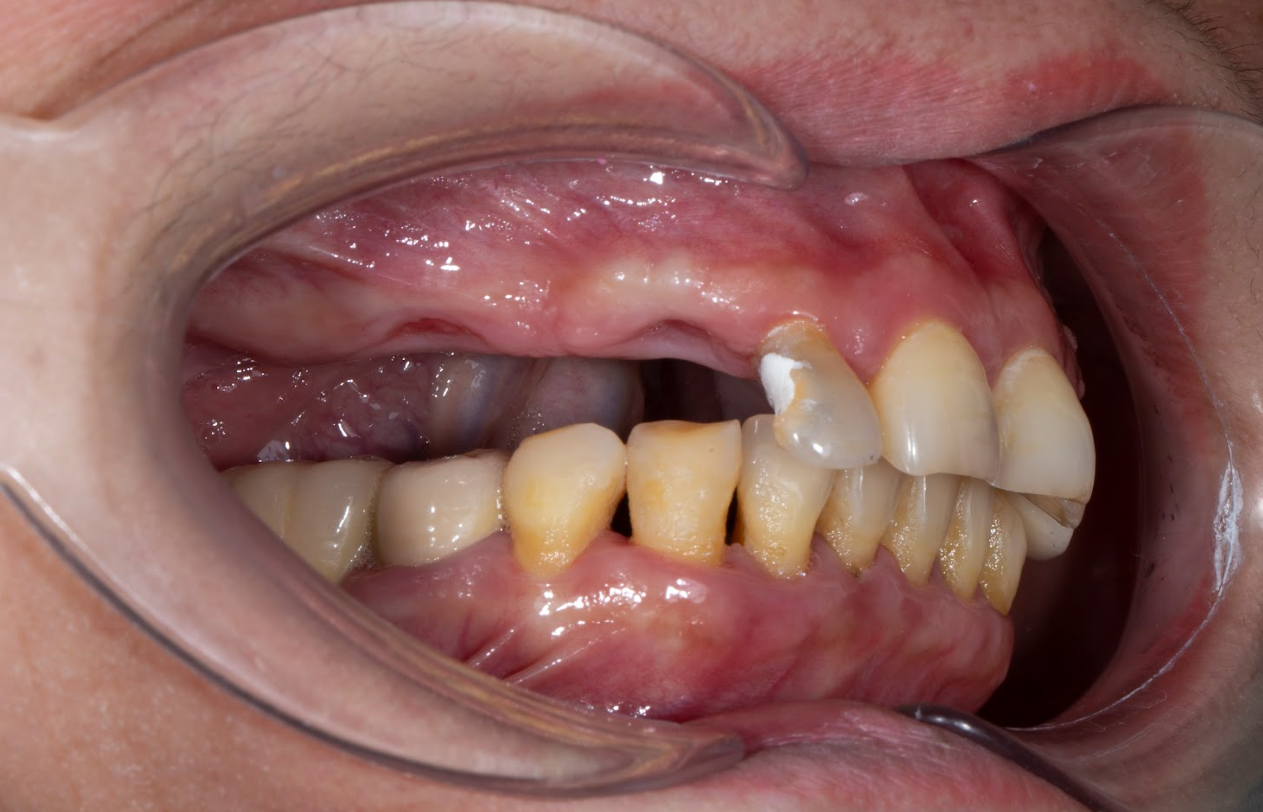

Cô Đinh Thị Anh Đào có cụm răng mất 5 răng liên tiếp cần trồng 3 trụ, làm 5 răng lên trên